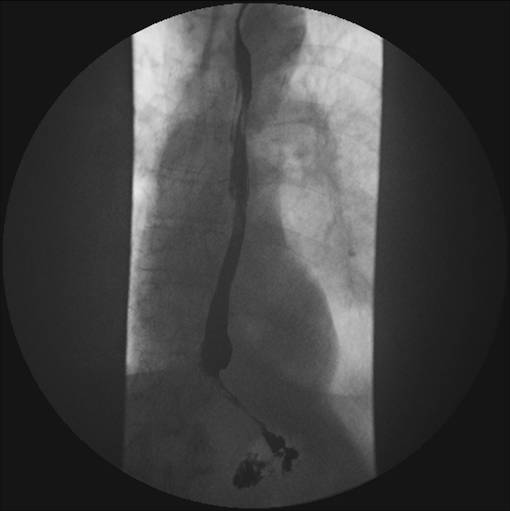

Kontrast på vej ned gennem den øverste del af øsofagus